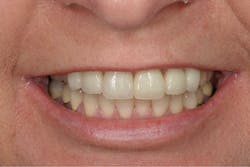

A 52-year-old female patient presented to my office with recent porcelain restorations that had been placed on her upper six anterior teeth. Besides her complaint of the bite feeling different, her main concern was that her speech was off, especially her s sounds. She stated these problems occurred after the final crowns were placed. Further questioning also revealed that she was unhappy with color and shape (figures 1–3). A full examination was completed, including x-rays and photographs, and periodontal, TMJ, occlusion, and dentition evaluations. She had excellent oral health and her dental issues were all related to her occlusal and esthetic complaints.

Figure 1: Anterior smile view of the patient’s original restoration